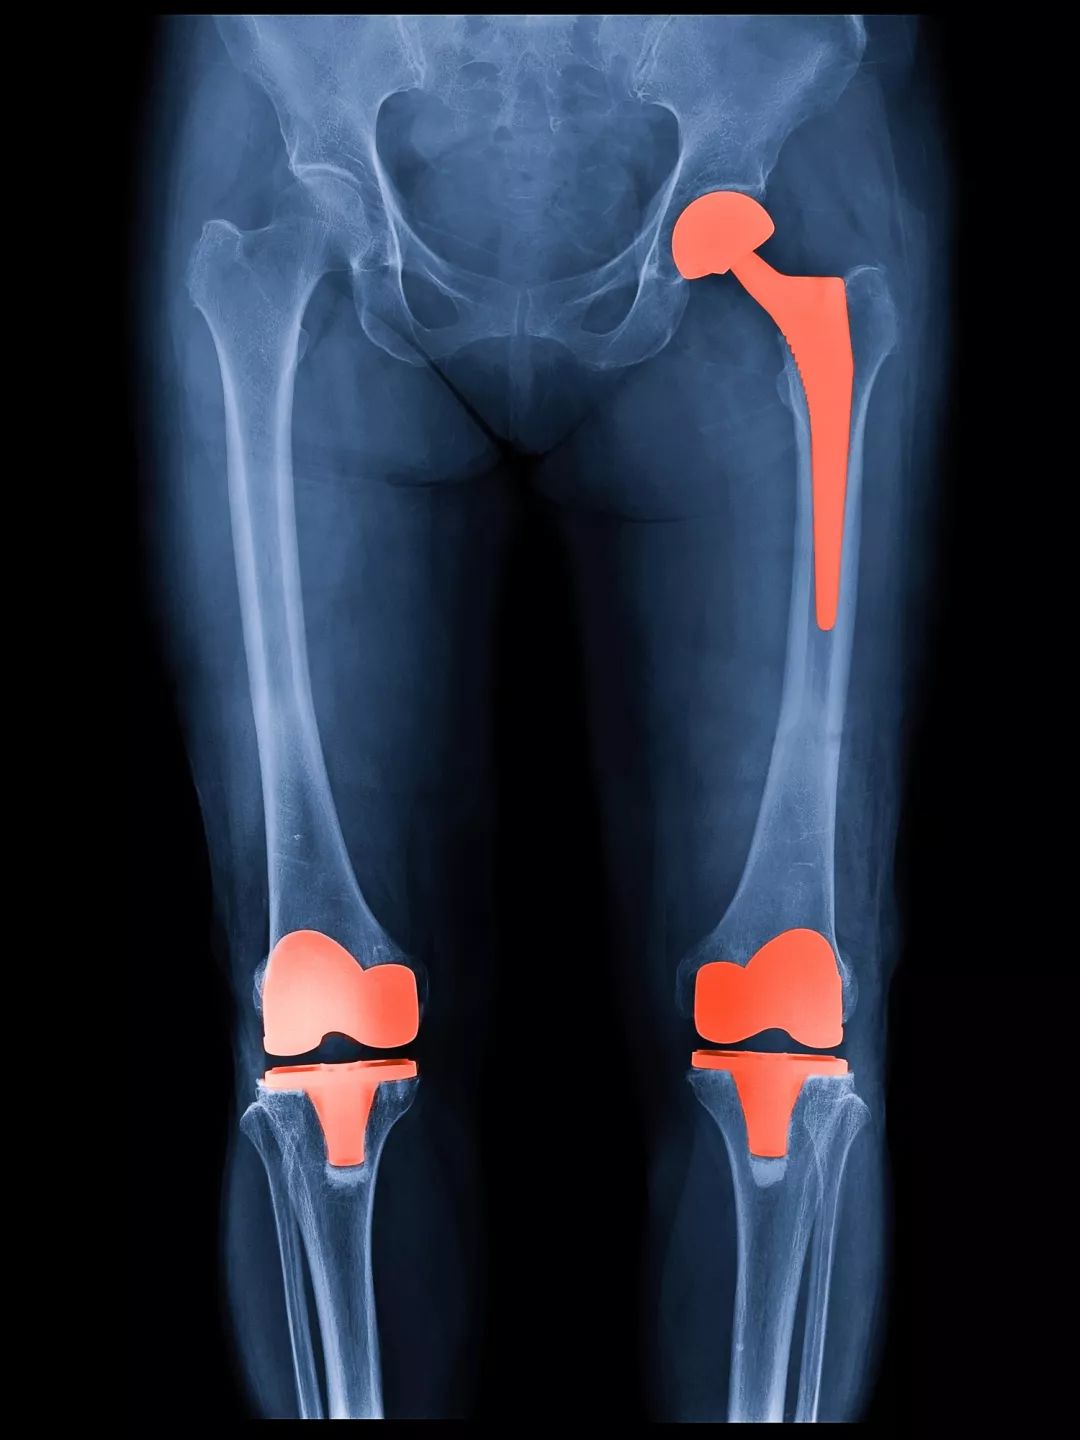

重建性手术:人工关节置换手术。包括全膝置换、单髁置换、髌股关节置换等。

自上世纪八十年代前北大人民医院吕厚山院长将膝关节置换术引入国内以来,经过几十年的发展,目前这项技术已经非常成熟,全国每年光膝关节置换就要开展数十万例,成功案例不胜枚举。关节置换术也被誉为上世纪最伟大的三大医疗技术发明之一,成功解决了各种终末期关节炎、晚期股骨头坏死等原本无法解决的医疗难题。

当然,置换的关节假体是有使用寿命的,如果年龄较年轻,比如低于55岁,甚至是50岁,需要详细的评估利弊,再做选择。